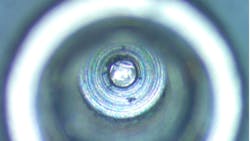

Of the seven major dental implant brands inspected, four contained visible material under magnification (57%), primarily located within the screw channel and connection (figure 1). Debris was also seen in the base of the screw channel in another brand-new implant (figure 2).